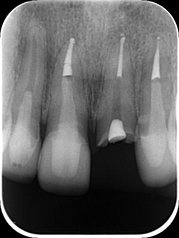

下のレントゲン写真は、脱離した歯の根管内に薬を詰めた状態です。

レントゲン写真は、クラウンが脱離した歯の根管治療後です。ファイバーコア・オールセラミックスクラウンを装着した両隣の歯は経過良好と思われます。